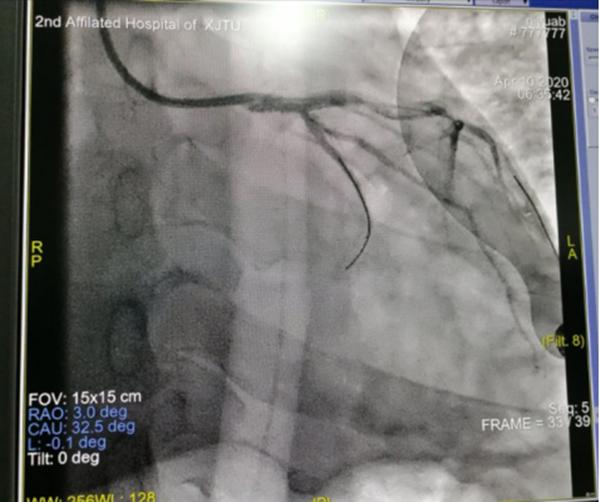

4月10日的凌晨2点钟,熟睡中的韩先生突然惊醒,心前区剧烈的疼痛伴随着难耐的胸闷气短,让正处壮年既往十分坚强的他产生了濒死的恐惧感,赶来的家属惊慌地拨打了120急救电话,将他送到了整合心血管病院。入院当时便出现了恶性心律失常、意识丧失,心内科薛嘉虹副主任医师就地组织抢救,心电图提示冠脉左主干病变,这在冠脉病变中属于非常严重的一种类型,随时有猝死风险,经与家属迅速有效沟通后紧急转运至导管室行冠脉介入治疗,考虑病情危重,心内科联系心外科协助抢救,心外科王春亚副主任医师、牟明超医师立即行气管插管接呼吸机辅助呼吸,并进行循环监测,为手术保驾护航。心内科薛嘉虹副主任医师、王新宏副主任医师娴熟操作,迅速植入主动脉内球囊反搏(IABP)装置辅助循环后行冠脉造影+冠脉支架植入术,手术历时1小时余顺利结束,术后的他仍意识模糊、四肢湿冷、血压难以维持、反复出现恶性心律失常,考虑心脏泵功能衰竭心源性休克,病情极其凶险,遂转入重症监护设施相对更加完备的心外科监护室,由王春亚副主任医师、王宇医师所在心脏重症团队继续监护治疗。冠脉造影术中发现患者冠脉左主干自起始部完全堵塞,心脏前壁运动幅度低,结合实验室检查心脏损伤指标测值超过可测定的上限等化验结果,提示心肌梗死面积大,近期可能突发乳头肌断裂、室间隔穿孔、左室游离壁破裂等紧急且危及生命的心脏机械并发症,病情比想象中的更加危重,这是一场与死神的生死较量,在全力抢救的同时,心外科全体医护人员共同在心里为他祈福。

冠脉病变开通后